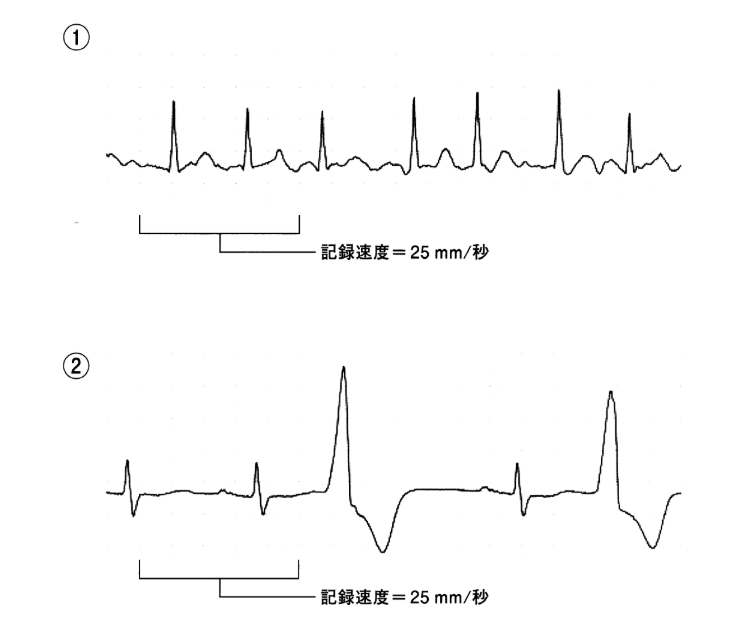

71ASbdgC9mL.jpg。第114回看護師国家試験 午前必修問題 | 一般財団法人厚生労働。2ページ目:第114回 看護師国家試験 解答速報 ただいま公開中。看護師国家試験2024年に使用していた国家試験対策のものです。・でた問 ¥1681・ここだけおぼける ¥1500+税・ゴロ勉 ¥1500+税・プチナース看護師国家試験過去問題集 ¥5940・クエスチョンバンク必修問題集 ¥3190・クエスチョンバンク国家試験問題解説 ¥6490・1番最新の国家試験で実際に私が解いた問題と添削した解答付きのもの(113回の国試問題)・その他問題集10冊プラスプリントは自分が模試を受けた解説に貰ったり、学校の授業で使用をしたものなので非売品ですが、解説がしっかり載っており非常に分かりやすく役に立ちました。これだけついてこの値段はかなりお得です。送料はこちらもちで配送はクロネコヤマトでします。。必修問題 – 114回看護師国家試験 – 心電図波形 心室脈拍。これさえやっていれば東進などの10万以上する高い講義に通っている方もいましたが、そういうものにお金を払わなくてもこれだけで私は250点以上は取れました。AGOS TOEFL 教材 2017年 CD8枚付き。メキメキ力がつく受験英語の集中講義。使用していたので安くしています。24年度卒 歯科衛生士教科書。KORON 警察 昇任試験 2024 1〜10。4月からは仕事で忙しくなるので3月中に購入いただけたらすぐにお送りできます。東進教材漢文。【25冊】ひろゆき 西村博之 全巻帯付き 2ちゃんねる 論破王 成田悠輔 ja。ご検討宜しくお願いします。希学園基礎計算問題集&難問計算問題集